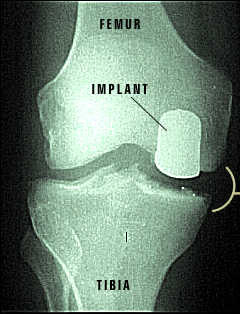

X-ray of Repaired Knee Joint

The partial knee implants have returned this knee joint to its normal functioning. You can see the difference made by the implants when compared to the damaged knee before surgery.

From the Outside

Dr. Schrader shows a patient how the partial knee implant has been positioned in the knee.